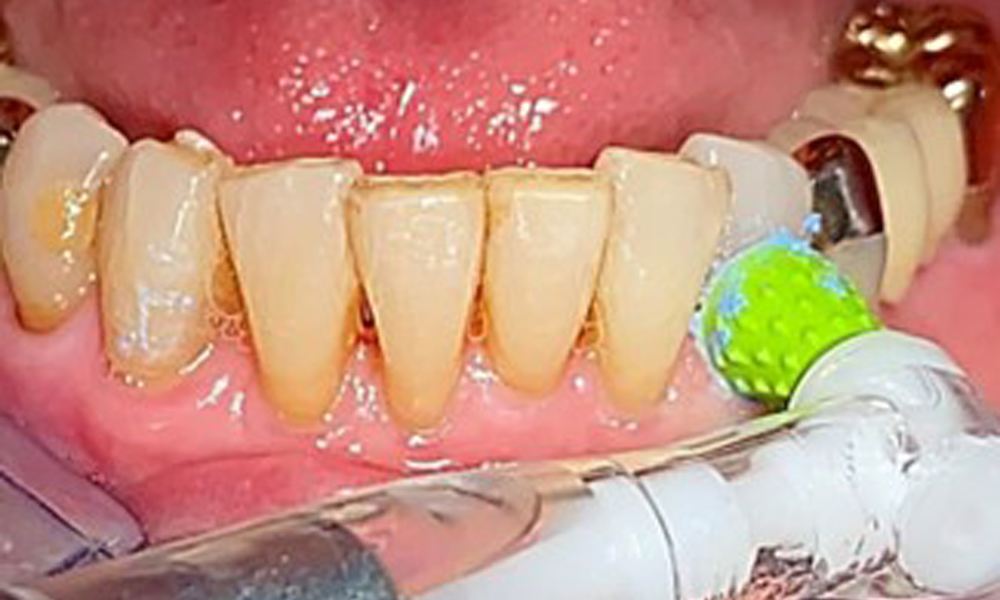

An air polishing system should be used with low-abrasive powder to remove biofilm from the restoration margins, interdental areas and implant surfaces (Fig. 12). Selective polishing (Fig. 13) should be used to smooth any less sensitive areas, as this decreases bacterial reattachment (9).

Interdental cleaning with brushes (Fig. 9) or dental floss is just as important as cleaning the tongue.